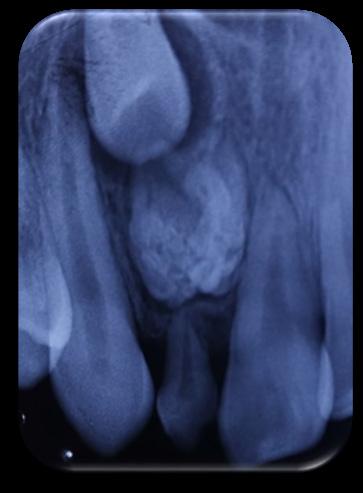

DISCUSIÓN

Tomando en cuenta nuestro caso clínico, los estudios histopatológicos determinaron que estamos frente a un proceso inflamatorio crónico inespecífico con fibrosis marcada, su extirpación fue exitosa sin ningún tipo de complicaciones dentro de la cirugía y del postoperatorio; Zambuzzi et al reportaron en un estudio que la hidroxiapatita natural de hueso bovino promueve un ambiente adecuado para la adhesión, proliferación y diferenciación de osteoblastos, lo cual lleva a una adecuada resolución del hueso (3); desde otro ángulo Chiapasco A. et al comparan la regeneración de cavidades quísticas mediante esponjas de colágeno (mantenedoras del espacio y estabilizadoras) y hueso liofilizado desmineralizado de cadáver; no encontraron diferencias estadísticamente significativas entre ambos grupos a los dos años, lo que confirma que en cualquier caso se presentará buena cicatrización ósea posterior a la quistectomías, al utilizar materiales aloplásticos, injertos o la propia formación ósea espontánea; ambos procedimiento utilizados en nuestro paciente (4).

RIIS UNIVALLE. Jul-Dic. 17(43), 2022; ISSN: 2075-6208 105 Aplicación de biomateriales post exeresis en un quiste inflamatorio radicular Adrián-Hurtado y cols.

Figura 9. Obtención del Sticky bone (SB), mezcla del A- PRF más el hueso bovino.

Hernández R. et al concuerdan con que el uso de injertos óseos es un método seguro, simple, eficaz y que además el odontólogo puede emplear para diversos defectos óseos alveolares, siempre y cuando sea considerado su sitio de colocación ya que esto influye directamente con el éxito del tratamiento. En sus tres reportes de casos pudo evidenciar que el uso de injertos promovió su buena oseointegración y presentó un alto nivel de biocompatibilidad, además ninguno de estos tres autores difiere en sus opiniones (5) (9) (10).

Cuando existe pérdida de tejido óseo extenso es importante utilizar biomateriales que produzcan osteoconducción, osteoinducción y osteogénesis, puesto que estos tienen la capacidad de estimular

REFERENCIAS BIBLIOGRÁFICAS

la formación ósea de una manera más rápida; dependiendo del tipo de material veremos que la formación ósea será más adecuada, tanto en volumen como en calidad; con esto no tratamos de indicar que la recuperación fisiológica no será buena, sino que esta tarda más tiempo, en contraste con el uso biomateriales y el aumento de densidad ósea; debido a la extensión de la cavidad, el relleno de la misma con el Sticky bone y cubrir con una membrana de pericardio porcino, se espera que cumplan la función osteoconductora en la cavidad. Basándonos en los estudios y revisiones recientes, esperamos buenos resultados en nuestros pacientes, debido a que el tiempo de neoformación dura aproximadamente 6 a 8 meses, por lo cual aún se encuentra en proceso.

1. García, A., Buljadón, A., & Rodríguez, A. (Febrero de 2015). Lesiones periapicales. Diagnóstico y Tratamiento. Avances en Odontoestomatología, XXXI(1), 31-42. Recuperado el 9 de Juio de 2018, Doi: https://doi.org/10.4321/S0213-12852015000100005

2. Swennen G, Dempf R, Schliephake H. Cranio-facial distraction osteogenesis: a review of the literature. Part II: Experimental studies. Int J Oral Maxillofac Surg. 2002 Apr; 31(2): 123-35. doi: https://doi.org/10.1054/ijom.2002.0225

3. Rebolledo M, Harris J, Higgins E, Molinares L. Cicatrización y regeneración ósea de los maxilares después de una quistectomía: reporte de un caso y revisión de la literatura. Univ Odontol. 2011 Jul-Dic; 30(65): 71-78 Recibido para publicación: 15-05-2011 Correcciones recibidas: 09-09-2011 Aceptado para publicación: 11-10-2011 Disponible en http://www.javeriana.edu.co/

4. Zambuzzi WF, Ferreira CV, Granjeiro JM, Aoyama H. Biological behavior of pre-osteoblasts on natural hydroxyapatite: a study of signaling molecules from attachment to differentiation. J Biomed Mater Res. 2011 May; 97(2): 193-200. Epub 2011 Mar 10. Doi.10.1002/jbm.a.32933 https://doi. org/10.1002/jbm.a.32933

5. Chiapasco M, RossiA, Motta JJ, Crescentini M. Spontaneous bone regeneration after enucleation of large mandibular cysts: a radiographic computed analysis of 27 consecutive cases. J Oral Maxillofac Surg. 2000 Sep; 58 (9): 942-8. Discussion 949. Doi https://doi.org/10.1053/joms.2000.8732

6. Edgar Eduardo Serrano Mejía Trabajo de grado para otorgar el título de Odontólogo Director Nohora Camila Rúgeles Páez Esp. Implantología oral y reconstructiva Universidad Santo Tomás, Bucaramanga División de Ciencias de la Salud Faculta de Odontología 2020. http://hdl.handle. net/11634/20496

7. Block MS. The processing of xenografts will result in different clinical responses. Journal of Oral and Maxillofacial Surgery 2018. Doi. 10.1016/j.joms.2018.10.004

8. Johnson, B., Fayad, M., & Witherspoon, D. (2011). Cirugía Perirradicular. En K. Hargreaves, & S. Cohen, Vías de la pulpa (págs. 720-755). Barcelona, España: Elsevier Mosby. Doi. https://doi. org/10.1016/B978-0-323-06489-7.00021-7

9. Morales, D., & Vila, D. (2016). Regeneración ósea guiada en Estomatología. Revista Cubana de Estomatología, LIII(1), 67-83. Recuperado el 17 de Julio de 2018, de http://scielo.sld.cu/scielo. php?script=sci_arttext&pid=S0034-75072016000100008

10. Rebolledo, M., Harris, J., Higgins, E., & Molinares, L. (2011). Cicatrización y regeneración ósea de los maxilares después de una quistectomía: reporte de caso y revisión de la literatura. Universitas Odontológica, 30(65), 71-78. Obtenido de http://www.javeriana.edu.co/universitasodontologica

RIIS UNIVALLE. Jul-Dic. 17(43), 2022; ISSN: 2075-6208 106 Aplicación de biomateriales post exeresis en un quiste inflamatorio radicular Adrián-Hurtado y cols.

DOI: https://doi.org/10.52428/20756208.v17i43.390

Inclusión dentaria por un odontoma compuesto

Dental inclusion by a compound odontoma

Javier Adrian Burgos 1. Francis Daniela Argandoña Ortiz2. Gabriela Adriana Lara León3

1Medico cirujano, Cirujano Dentista, Esp. En Cirugía Bucal, Msc. En Implantología Oral, Docente Univalle Sub- Sede La Paz jadrianb@univalle.edu

2 Estudiante de la Carrera de Odontología, Universidad Privada del Valle La Paz, aof2015031@est.univalle.edu